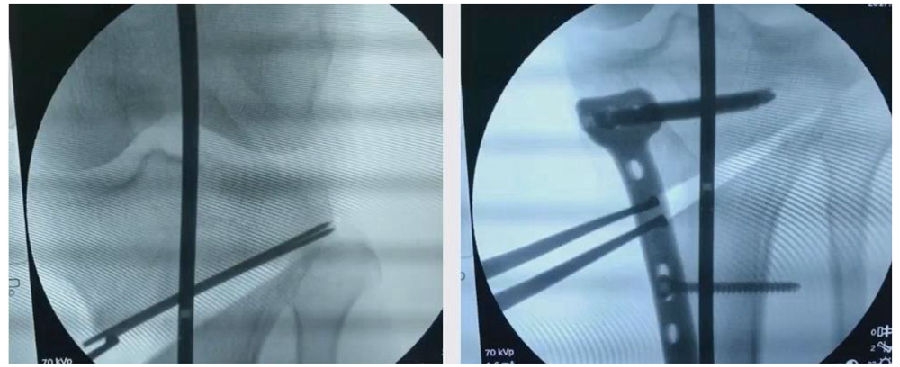

(3)拉力钉技术

第3个原因和拉力钉使用技术有关。拉力螺钉的使用是希望在合页端产生一个加压的效果,如果拉力螺钉使用过度,会出现合页端拉断的情况,导致Ⅱ型骨折。所以要求拉力螺钉在使用时加压不要过度,通常当钢板有轻微的变形即可,不要过度加压。

首先要把截骨撑开钳拿下来,此时骨折端会自动复位,然后再由外向内侧打入一颗拉力螺钉,将胫骨平台做临时固定,然后再进一步的用摆锯锯或是用骨刀打,保留1cm的合页,最后再进行撑开,做内固定。同样要求患者做结构植骨加延迟负重。

截骨偏前,截骨线过短;Ⅲ型骨折;保留1cm合页

结构植骨,外侧拉力钉固定